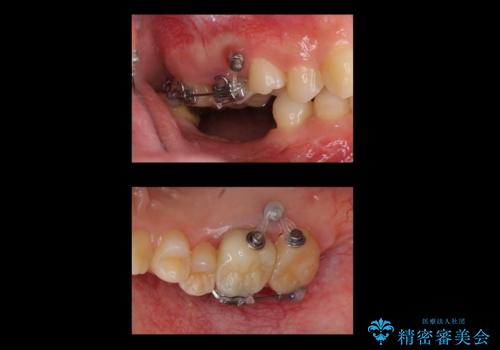

右上に部分矯正を行い、クリアランスを確保した後、右下にイプラントを2本埋入しています。

上の歯が伸びだしてきていたため、部分矯正を行い歯を移動させてから、向かい合わせの歯にインプラント治療を行っています。

右上第一大臼歯は六本木院の林院長に根管治療をお願いしました。